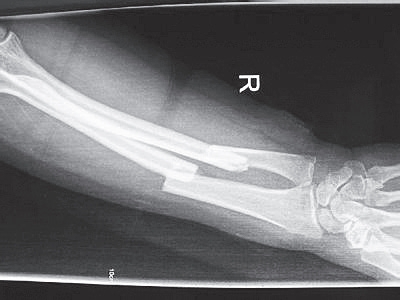

3.影像学检查(图10-1)。

图10-1 尺桡骨骨干骨折X线片